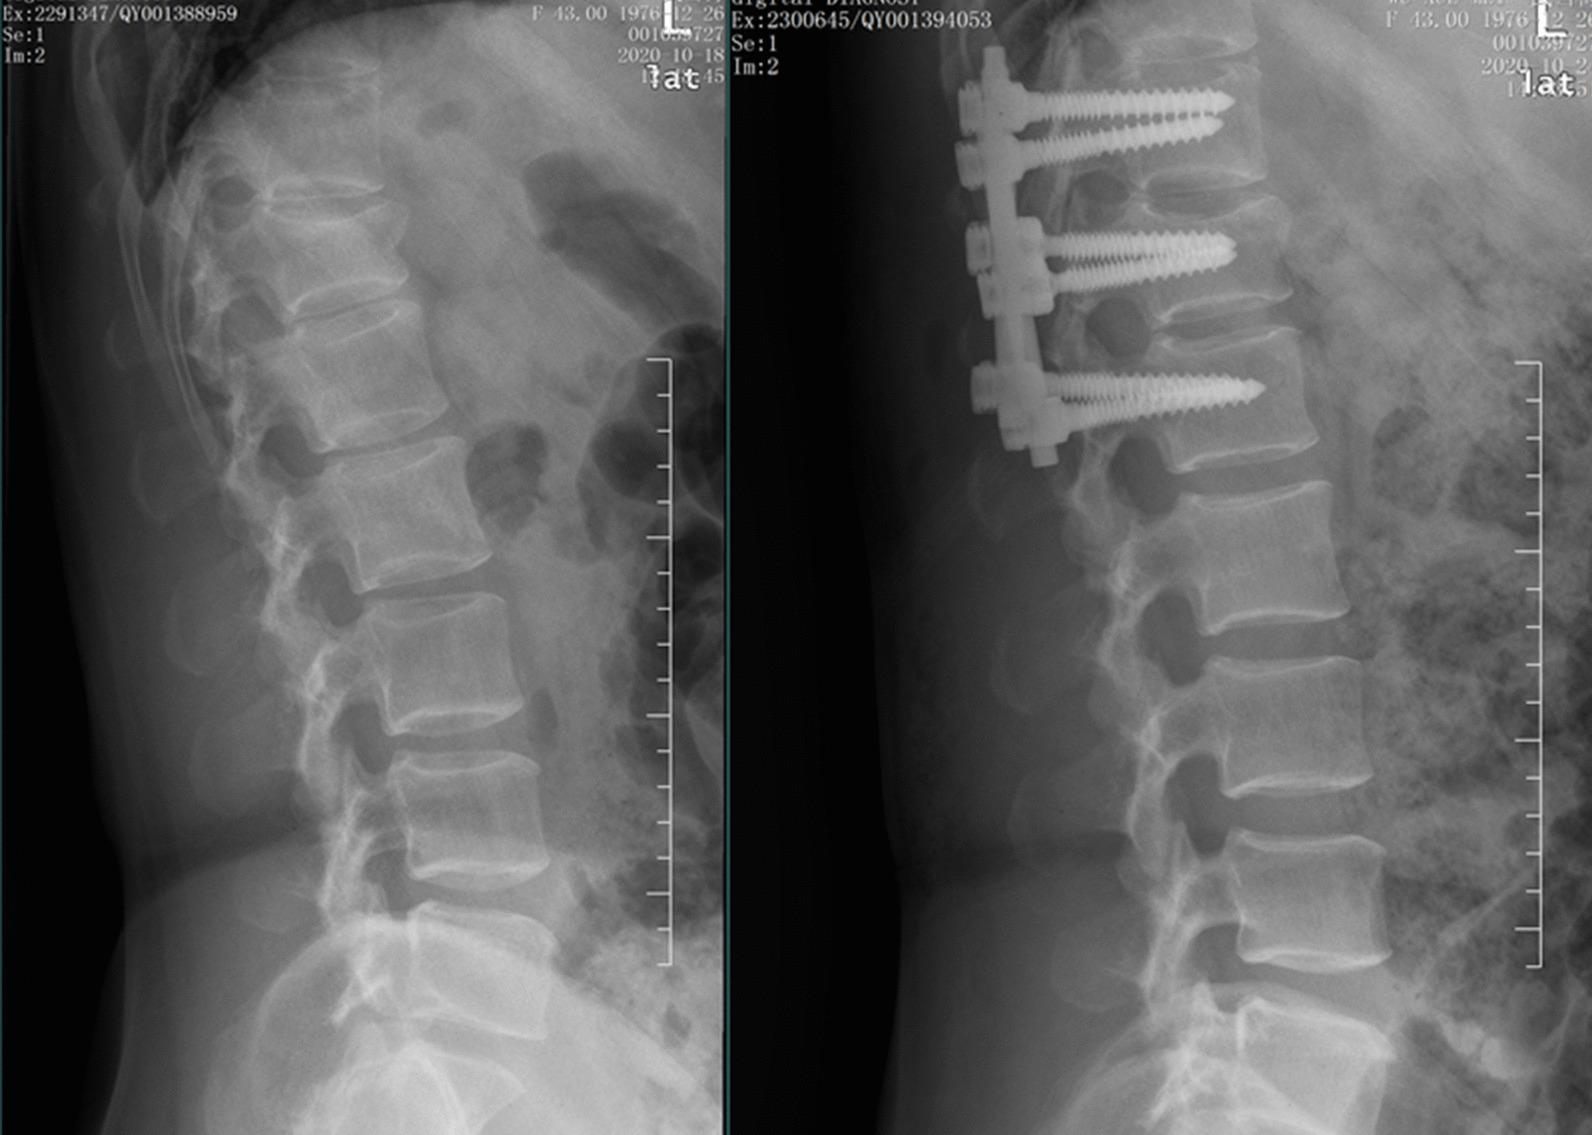

经皮椎弓根螺钉固定与微创 Wiltse 入路椎弓根螺钉固定治疗神经完整胸腰椎骨折的隐性失血:一项回顾性研究。

Hidden blood loss between percutaneous pedicle screw fixation and the mini-open Wiltse approach with pedicle screw fixation for neurologically intact thoracolumbar fractures: a retrospective study.

The aim of this study was to determine the proportion of hidden blood loss (HBL) in patients treated with minimally invasive surgery, and to compare the HBL between patients treated with percutaneous pedicle screw fixation (PPSF) and the mini-open Wiltse approach with pedicle screw fixation (MWPSF).

From January 2017 to January 2019, a total of 119 patients with thoracolumbar fractures were included in the analysis, of which 58 cases received PPSF and 61 cases received MWPSF. The clinical information and demographic results were collected and compared. And the HBL of the patients is calculated by the combination formulas of Nadler, Gross and Sehat.

Compared with the PPSF group, operation time of MWPSF is shorter. The fluoroscopy times are 13.6 ± 3.0 in PPSF group and 5.6 ± 1.6 in MWPSF group (p < 0.001). As shown in Table 3, the intraoperative blood loss in PPSF group is 31.9 ± 9.6 ml, which is significantly less than that in the MWPSF group (44.0 ± 14.9 ml). The HBL (445.7 ± 228.9 ml), and HBL% (91.2 ± 7.7%) of the PPSF group are significantly higher than that in the MWPSF group (P < 0.05). And the total blood loss (TBL) of the PPSF group (477.6 ± 228.8 ml) is also more than that in the MWPSF group (401.0 ± 171.3 ml).

Our results suggest that in the minimally invasive surgical treatment of thoracolumbar fractures, the perioperative HBL is much higher than visible blood loss (VBL). Although PPSF has less intraoperative blood loss, it has higher TBL and HBL than those of MWPSF. Compared with MWPSF, we should pay more attention to the postoperative anemia status of patients with thoracolumbar fractures undergoing PPSF surgery.

本研究旨在确定微创治疗患者的隐性失血量(HBL)比例,并比较经皮椎弓根螺钉固定(PPSF)和微创 Wiltse 入路椎弓根螺钉固定(MWPSF)患者的 HBL。

2017 年 1 月至 2019 年 1 月,共纳入 119 例胸腰椎骨折患者,其中 58 例行 PPSF,61 例行 MWPSF。收集并比较患者的临床信息和人口统计学结果。并采用 Nadler、Gross 和 Sehat 的组合公式计算患者的 HBL。

与 PPSF 组相比,MWPSF 组的手术时间更短。透视次数在 PPSF 组为 13.6±3.0,在 MWPSF 组为 5.6±1.6(p<0.001)。如表 3 所示,PPSF 组术中出血量为 31.9±9.6ml,明显少于 MWPSF 组(44.0±14.9ml)。PPSF 组 HBL(445.7±228.9ml)和 HBL%(91.2±7.7%)明显高于 MWPSF 组(P<0.05)。PPSF 组总失血量(TBL)(477.6±228.8ml)也多于 MWPSF 组(401.0±171.3ml)。

我们的结果表明,在微创治疗胸腰椎骨折中,围手术期 HBL 明显高于显性失血量(VBL)。虽然 PPSF 术中出血量较少,但 TBL 和 HBL 均高于 MWPSF。与 MWPSF 相比,我们应更加关注行 PPSF 手术的胸腰椎骨折患者术后贫血状态。